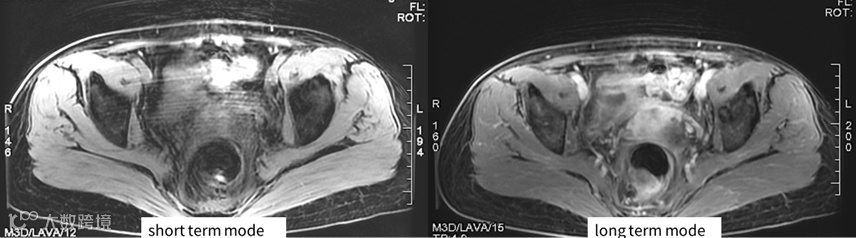

图4说明:这里对比的是当采用2个NEX时通过改变两次激励过程中K空间数据的采集方式来减少呼吸导致的盆部扫描时呼吸导致的运动伪影。只有在采用2个NEX时才能采用long term模式。